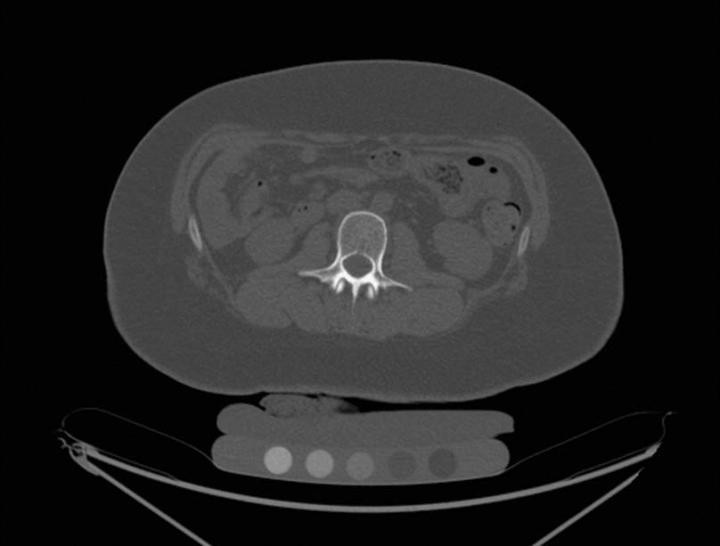

Tiến sĩ Bredella nói: “Ở người lớn, phẫu thuật cắt dạ dày có thể ảnh hưởng lâu dài đến xương, dẫn đến nguy cơ gãy xương cao hơn. "Chúng tôi muốn xác định tác động của việc cắt dạ dày được thực hiện đối với thanh thiếu niên trong những năm quan trọng khi khối lượng xương đang được tích tụ." Nghiên cứu đã kiểm tra 52 thanh thiếu niên bị béo phì mức độ trung bình đến nặng, 26 người trong số họ đã được phẫu thuật cắt dạ dày. 26 người khác nằm trong nhóm đối chứng. Tuổi trung bình là 17,5 tuổi và chỉ số khối cơ thể (BMI) trung bình là 45. BMI từ 30 trở lên được coi là béo phì. Ba mươi tám người tham gia nghiên cứu là các cô gái. Trước và 12 tháng sau khi cắt dạ dày (hoặc không phẫu thuật), bệnh nhân được chụp CT định lượng cột sống thắt lưng, để định lượng thể tích mật độ khoáng xương. CT định lượng là một kỹ thuật có độ chính xác cao để phát hiện những thay đổi về thể tích mật độ khoáng xương sau khi giảm cân quá mức.

Các nghiên cứu gần đây đã chỉ ra rằng chất béo trong tủy xương phản ứng với những thay đổi trong dinh dưỡng và có thể đóng vai trò như một dấu hiệu sinh học cho chất lượng xương. Do đó, bệnh nhân được tiến hành soi phổ proton MR để định lượng mỡ tủy vùng cột sống thắt lưng.

Một năm sau khi phẫu thuật, những thanh thiếu niên trải qua phẫu thuật cắt dạ dày đã giảm 34 (+/- 13) kg, hoặc 75 (+/- 28) pound ( P=0,45 kg), trong khi không có sự thay đổi đáng kể về cân nặng ở nhóm đối chứng. So với nhóm đối chứng, bệnh nhân cắt dạ dày có sự gia tăng đáng kể chất béo trong tủy xương và giảm mật độ xương ở cột sống thắt lưng.